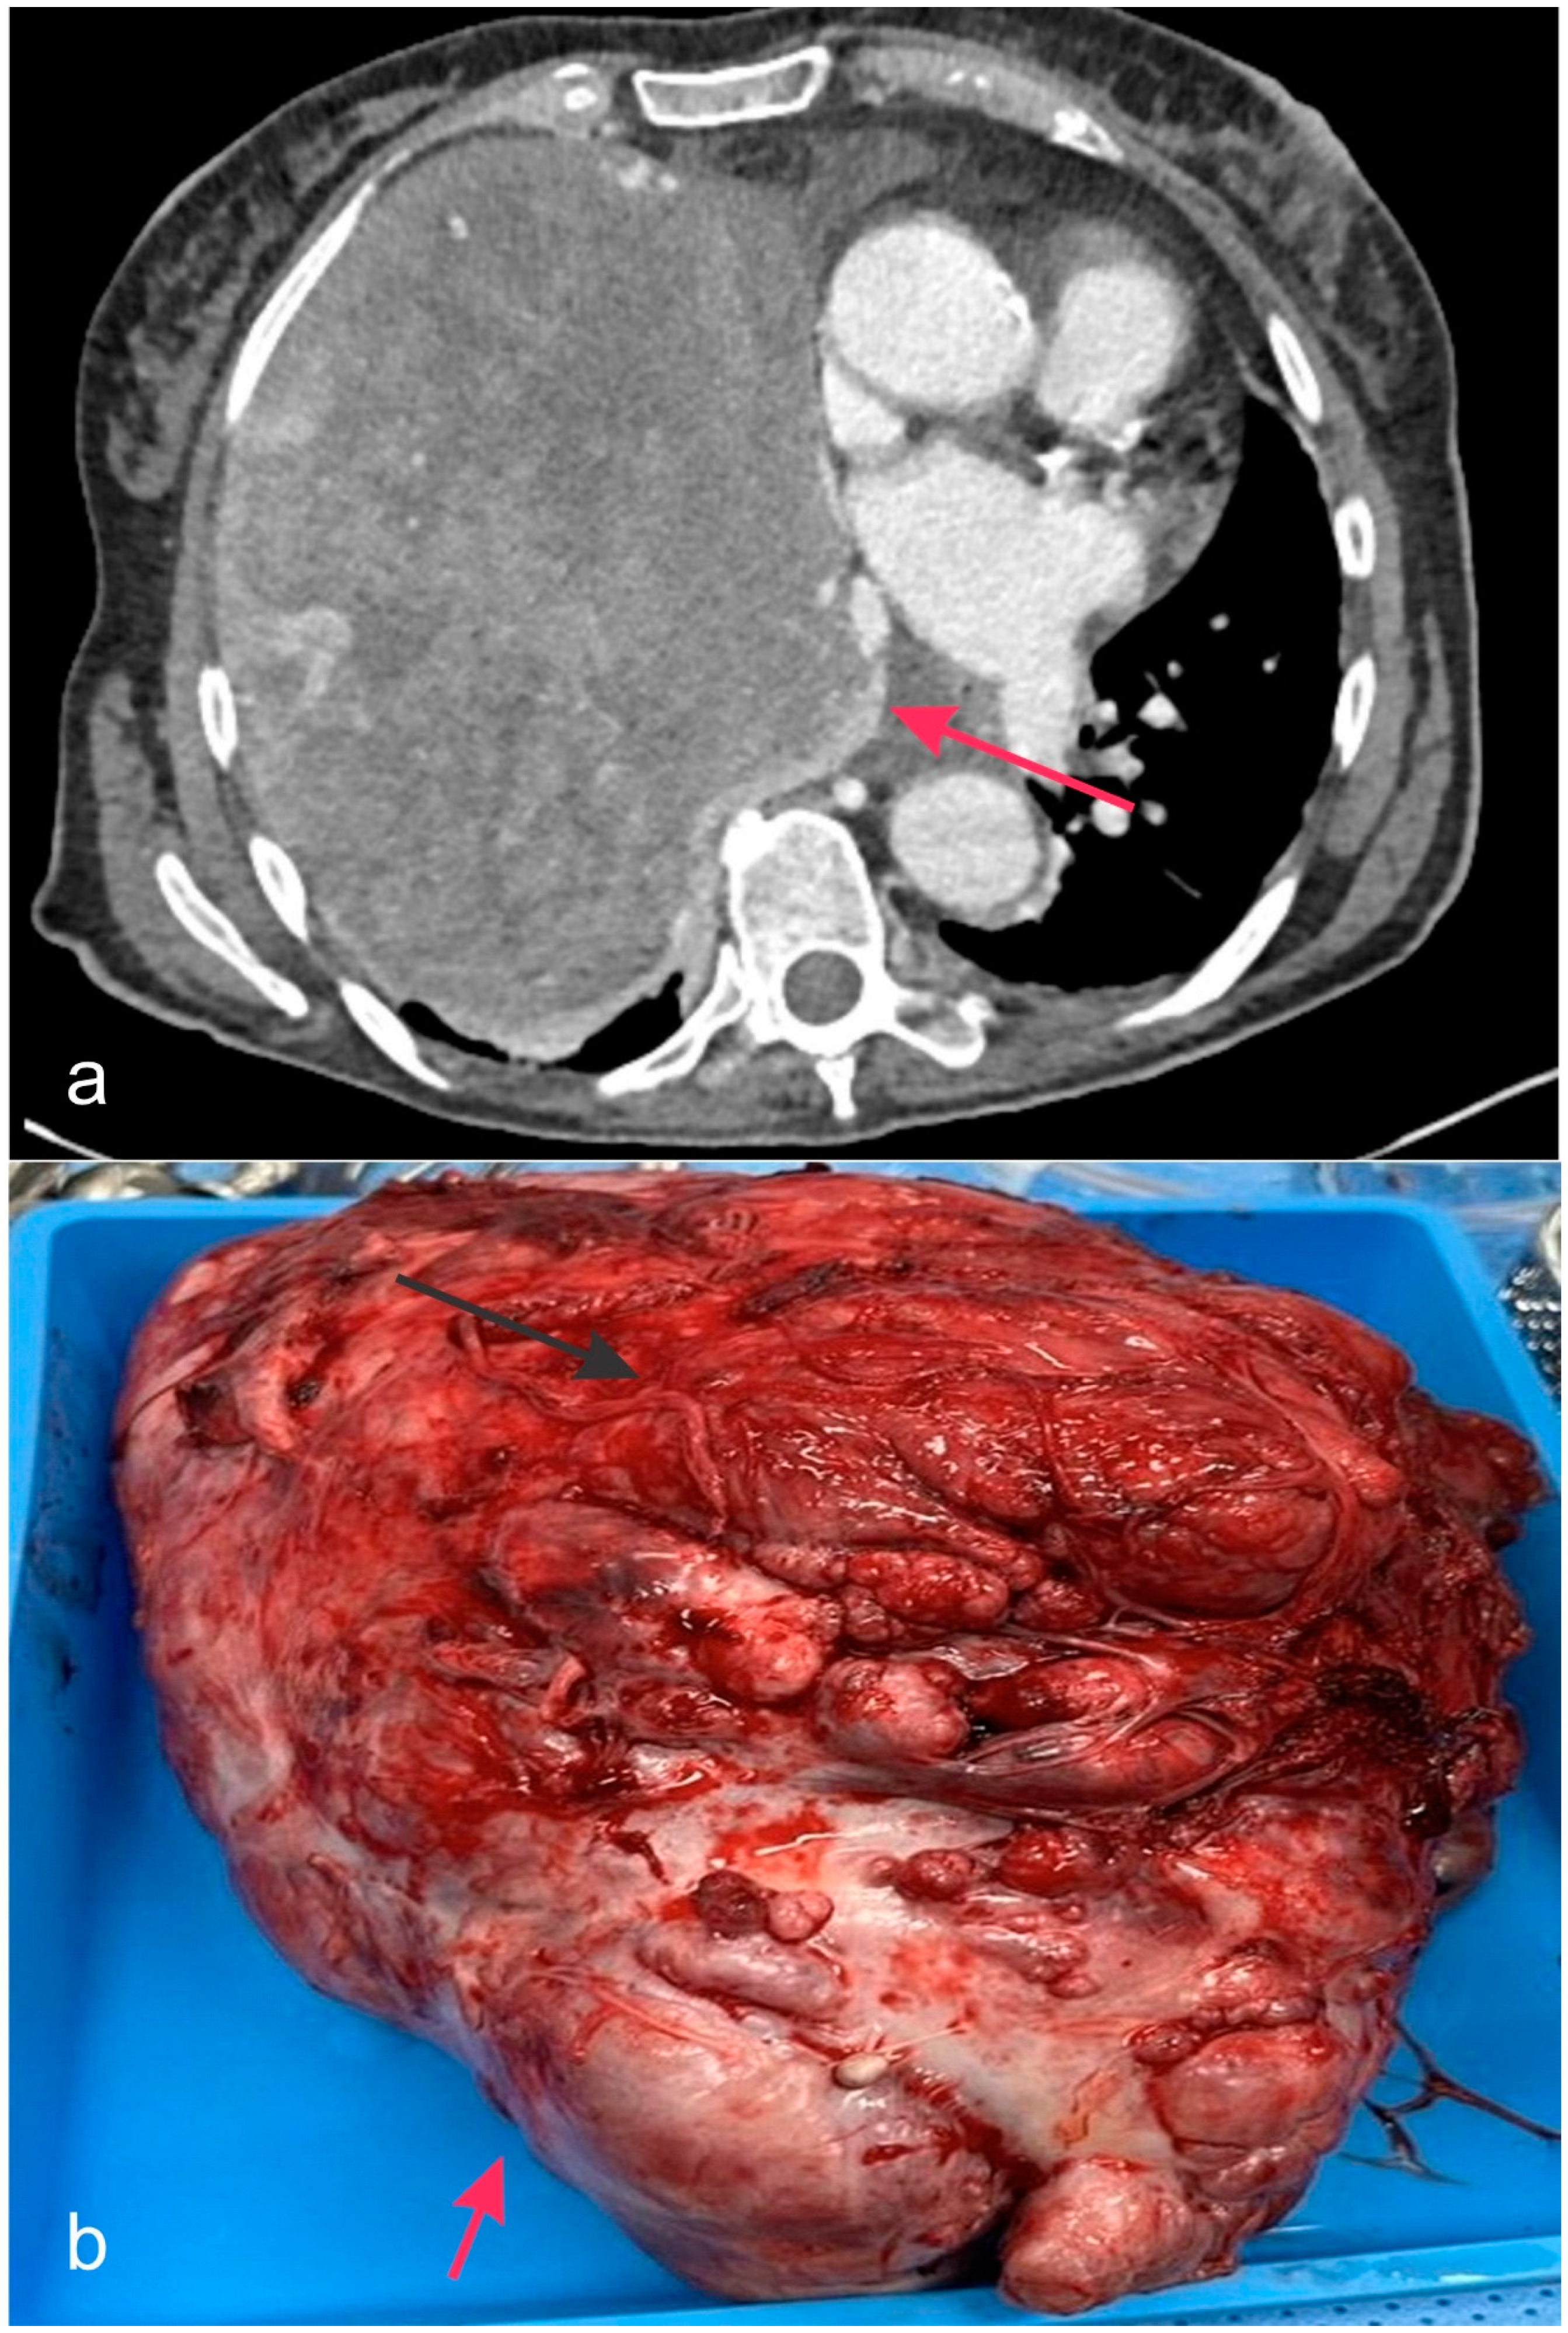

5. Disorders Associated with DICER1 Gene Mutations

6. DICER1 Syndrome